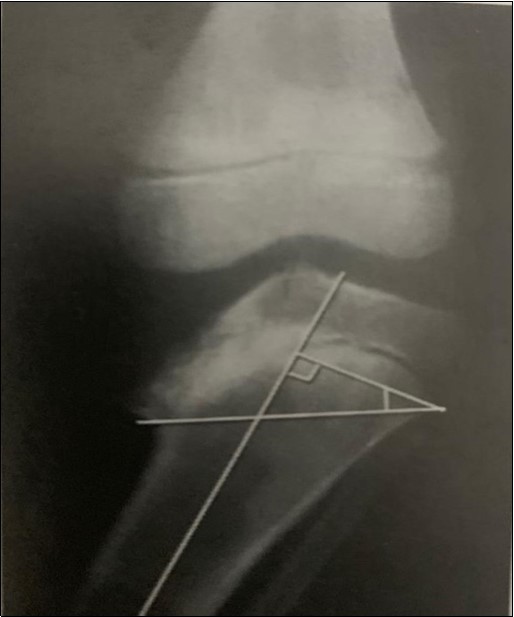

Figure2 depicts the measurement of the metaphyseo-diaphyseal angle which is another method for classifying the disease. A line is drawn perpendicular to the long axis of the tibia and another across the metaphyseal flare. The acute angle formed by these two lines should normally not exceed 11 degrees 7.

Figure 2.These classification systems are employed to aid diagnosis, monitor progression and to guide treatment of the disease 13